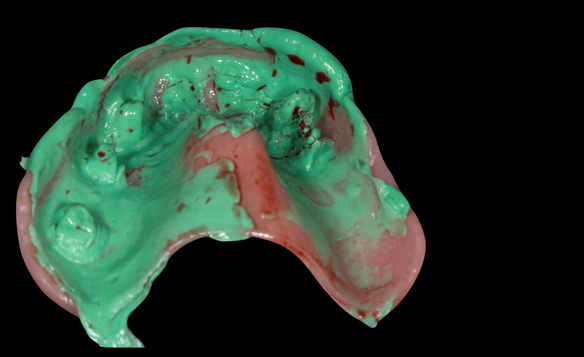

This newsletter describes in step by step detail Anne's transition from an immediate complete upper denture to a definitive complete upper denture.

The clinical situation and treatment process is shown in detail below with photographs. In addition, threre is a link to the a 45 minute webinar I gave explaing this case. I provided the clinical work and Rowan Garstang provided the technical work.